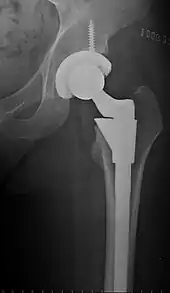

An X-ray showing a left hip (right of image) that has been replaced, with the ball of this ball-and-socket joint replaced by a metal head that is set in the femur and the socket replaced by a cup

Hip replacement is a surgical procedure in which the hip joint is replaced by a prosthetic implant, that is, a hip prosthesis. Hip replacement surgery can be performed as a total replacement or a hemi/semi(half) replacement. Such joint replacement orthopaedic surgery is generally conducted to relieve arthritis pain or in some hip fractures. A total hip replacement (total hip arthroplasty or THA) consists of replacing both the acetabulum and the femoral head while hemiarthroplasty generally only replaces the femoral head. Hip replacement is one of the most common orthopaedic operations, though patient satisfaction varies widely. Approximately 58% of total hip replacements are estimated to last 25 years.[1] The average cost of a total hip replacement in 2012 was $40,364 in the United States, and about $7,700 to $12,000 in most European countries.[2]